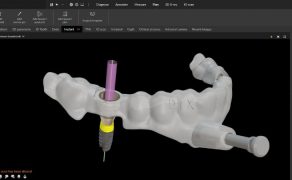

Postępowanie w przypadkach resorpcji wewnętrznej korzenia w zębach stałych

Summary: Internal root resorption (IRR) is a

particular category of pulp disease characterized by the loss of

dentine as a result of the action of clastic cells stimulated by

pulpal inflammation. This review article explains the etiology, the

prevalence of IRR, and, in addition to the clinical data, the

contribution of the three-dimensional imaging (CBCT) to the

diagnosis, the clinical decision, and the therapeutic management of

IRR. The authors discussed the various therapeutic options

including the orthograde or retrograde fillings of the root canal

resorption area. Root canal treatment remains the treatment of

choice of internal root resorption as it removes the granulation

tissue and blood supply of the clastic cells. The authors describe

with different clinical cases the modern endodontic techniques

including optical aids, ultrasonic improvement of chemical

debridement, and the use of alternative materials such as calcium

silicate combined with thermoplastic filling (warm gutta-percha).

In these conditions, the prognosis of the conservative treatment of

internal resorptions, even if root walls are perforated, is

good.